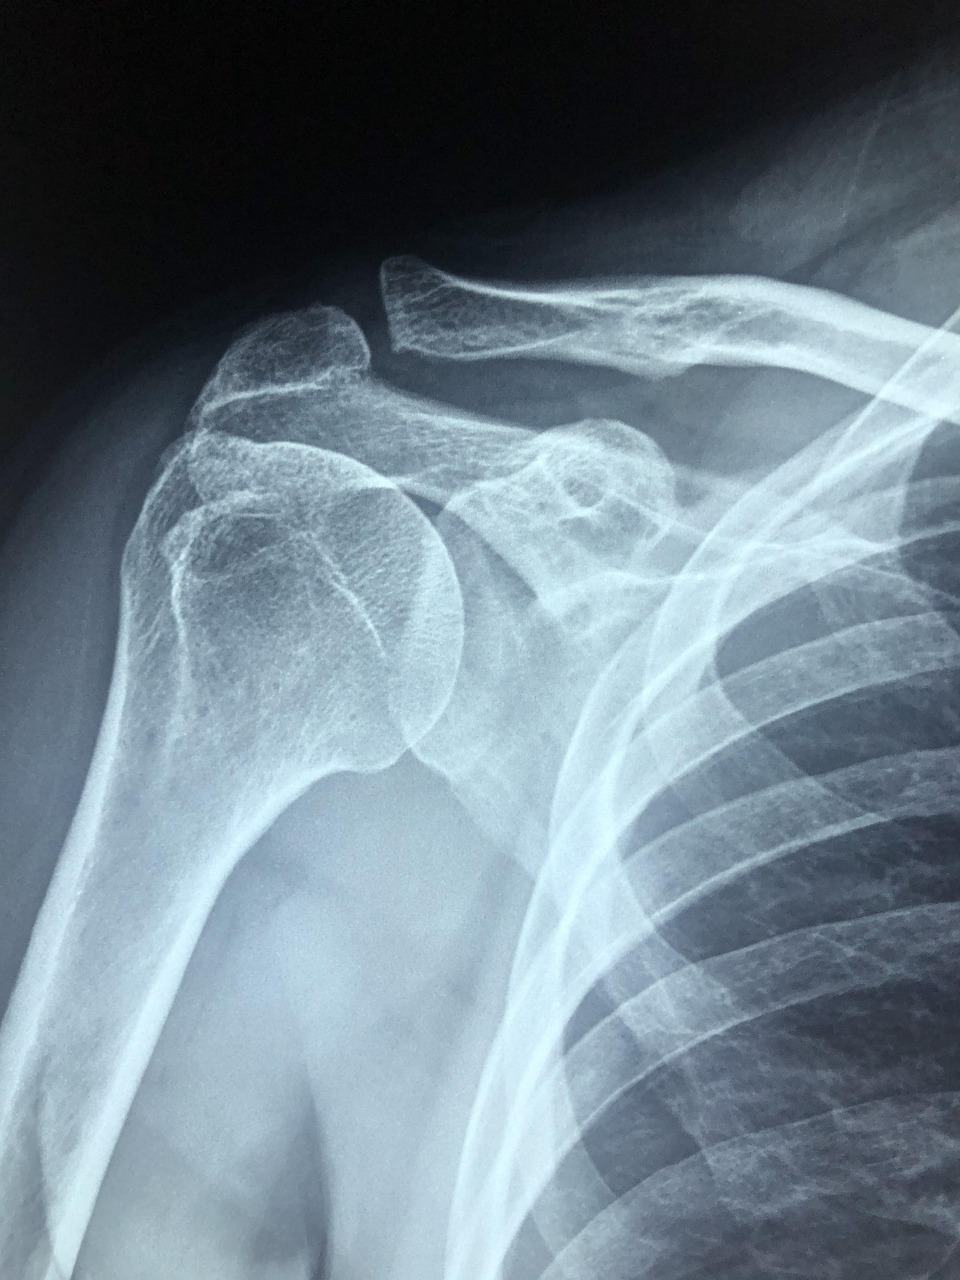

놀이터에서 놀던 아이가 미끄럼틀에서 떨어졌는데, 울음이 심상치 않았습니다. 그리고 팔을 움직이지 못하는 일이 일어났어요. 급하게 집 앞에 정형외과에 갔더니, 골절이 된 상태이며 아이는 수술할 수 없으며, 성장판 쪽도 침범할 수 있으니 큰병원에 가라고만 하고 어느 병원에 가야 할지는 알려주지 않습니다. 많이 당황하셨겠지만, 이런 경우에 대처할 수 있는 방법에 대해서 알아보려고 합니다.

어린이 뼈 끝에는 성장판이 있어 뼈 길이와 모양을 결정합니다. 따라서 뼈 끝 쪽에 골절이 생긴 경우에는 성장판이 손상되었는지 여부를 같이 확인해주어야 하기 때문에 소아정형외과 전문의 가 같이 봐주어야 정확한 판단이 가능합니다. 만약 성장판이 손상되면 팔다리 길이에 차이가 날 수 있으며, 변형이 발생할 수도 있습니다. 성인 정형외과 적으로 접근하여 수술하면 성장 장애를 남길 수 있기 때문에, 성장판 보존을 최우선으로 치료하는 소아정형외과 전문의를 찾아가시는게 좋습니다.